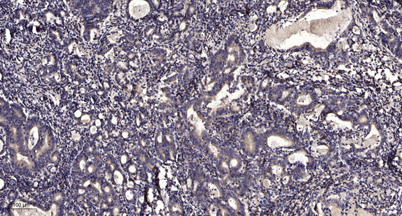

Applications IHC

Recomended Dilution IHC-p 1:50-300